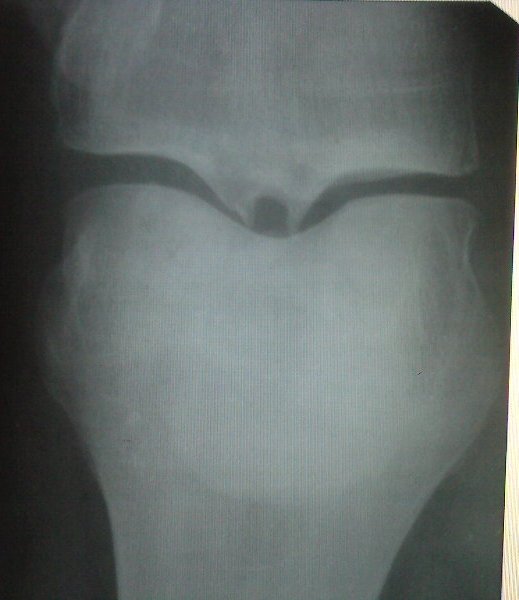

Добрый день.Сильные боли в колене начались осенью 2008 года при значительной нагрузке на ноги (ношение тяжести и длительная ходьба ).Обратилась к врачу, сделала рентген. Поставили диагноз: деформирующий артроз.Лечения никакого, только операция.Правда, назначили уколы (не помню названия), которые сняли воспаление. Потом прошла курс лечения "Терафлексом" совместно с "Зинаксином". Стало легче, ограничила нагрузку, боль успокоилась.В санатории лечила электрофорезом с применением крема "Карипаин", лазерным лучом. Грязями нельзя, потому, что имеет место варикозное расширение вен. Но все равно, чувствуется дискомфорт и незначительные боли , особенно при ходьбе по ступенькам. Неделю назад упала и ушибла колено. Пришлось сделать рентген. Сравнивая два снимка, вижу ухудшение. Обеспокоена, потому, что не знаю, что мне делать. Существуют ли методы лечения кроме оперативного вмешательства?Заранее очень Вам благодарна за Вашу помощь.